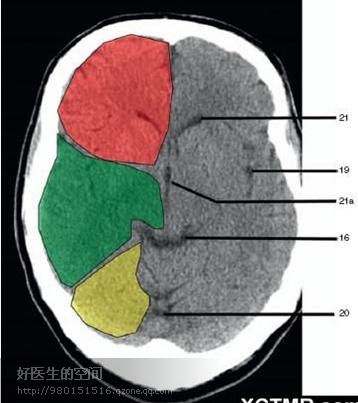

20、小脑上池 (Third ventricle) 21、侧脑室前角 (Frontal horn of lateral ventricle) 21a、第三脑室 (Third ventricle) 绿色部分为颞叶(Temporal Lobe),浅红色部分为额叶(Frontal Lobe),黄色部分为枕叶(Occipital Lobe)